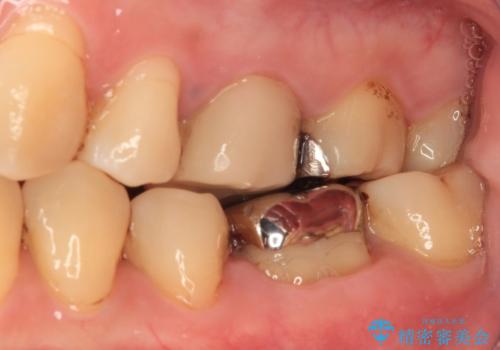

- 人と話す際に、下顎の奥にある銀歯が目立って気になるとのことで来院された患者様です。

左右の奥歯に銀歯のクラウンが装着されていたため、銀歯除去後に仮歯に置き換え、フルジルコニアクラウンにて補綴治療を行うこととしました。